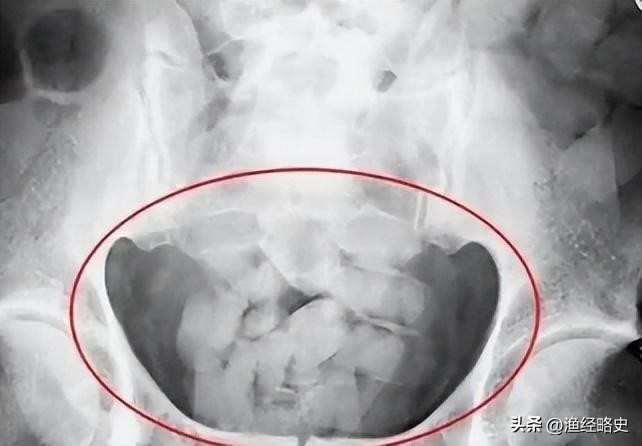

经验丰富的缉毒警见状直接将陶静带到了审讯室询问,她年纪太小又没有经过什么大事大非,光是审讯室的氛围都让她胆战心惊!缉毒警开口道:“你配合我们做一下检查吧,没事就会放你走的。”不一会儿一名缉毒警拿着一个扫描仪对着陶静一通扫描,最后发现她用体内藏毒的办法,藏了200g*毒冰**。

陶静冰冷的眼神逐渐开始回温:“是杨勇让我这么做的,说不会被发现,干一次以后就不不干了。”女警问:“那他是怎么让你参与运毒的?整个流程又是啥样的?”陶静说:“男女带*品毒**的克数不一样,女的一次带两百克藏进子宫,男的一次带一百克藏进肛门,*品毒**装进塑料袋里,女的从嘴里吃下去,男的直接从肛门塞进去,整个过程非常痛苦,一旦塑料袋破裂了就会死亡。”